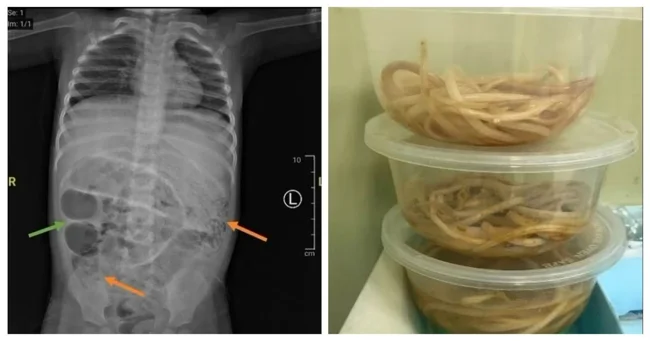

The young patient began vomiting worms, and an X-ray of his stomach showed gray masses, indicating an “intestinal obstruction.”

Surgeons performed a laparotomy — an incision into the abdomen — and found worms blocking three sections of the small intestine. The parasites were removed and sent to the lab for analysis.

This type of roundworm, known as ascaris, can grow up to 35 centimeters in length and live in the human intestine.